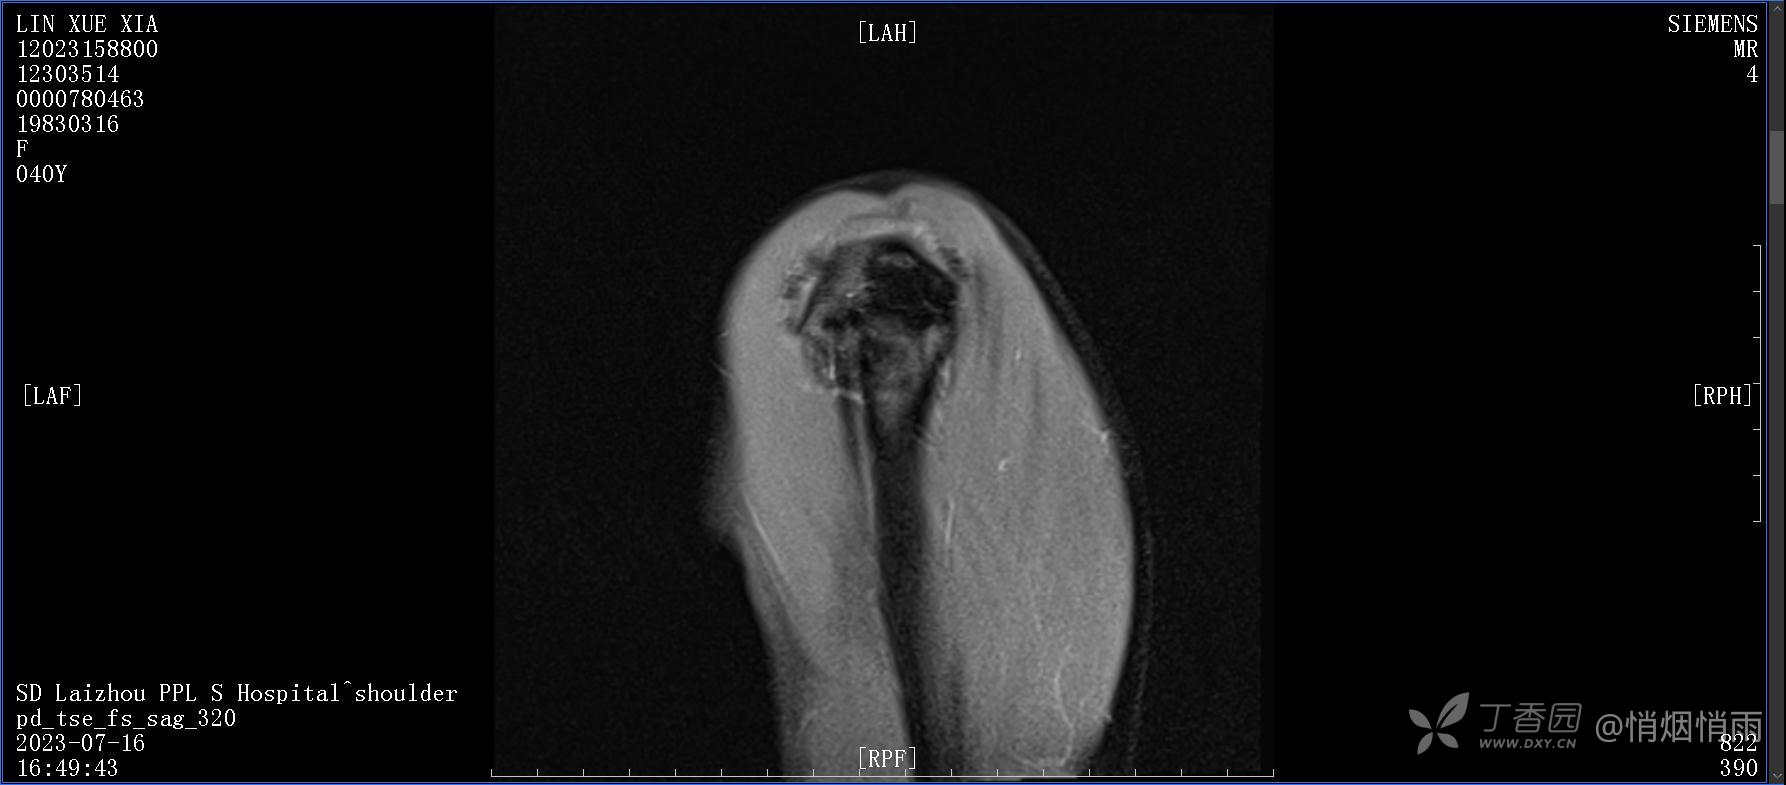

查体:右肩关节局部轻度肿胀,肩胛区压痛明显,痛处不固定,肩关节痛性活动受限,jobe test(+),lift -off test(+),中指、环指感觉较余指减退,余肢端感觉及血运情况可。

目前的诊断,暂时依据辅助检查诊为肩袖损伤,但是患者疼痛的性质和特点,却不是单纯的肩袖损伤所致。考虑过胸廓出口综合征,但是该疾病会出现肩胛区的疼痛吗?(由于考虑到费用的问题,没再进行下一步的检查)带状疱疹会有如此的症状吗?